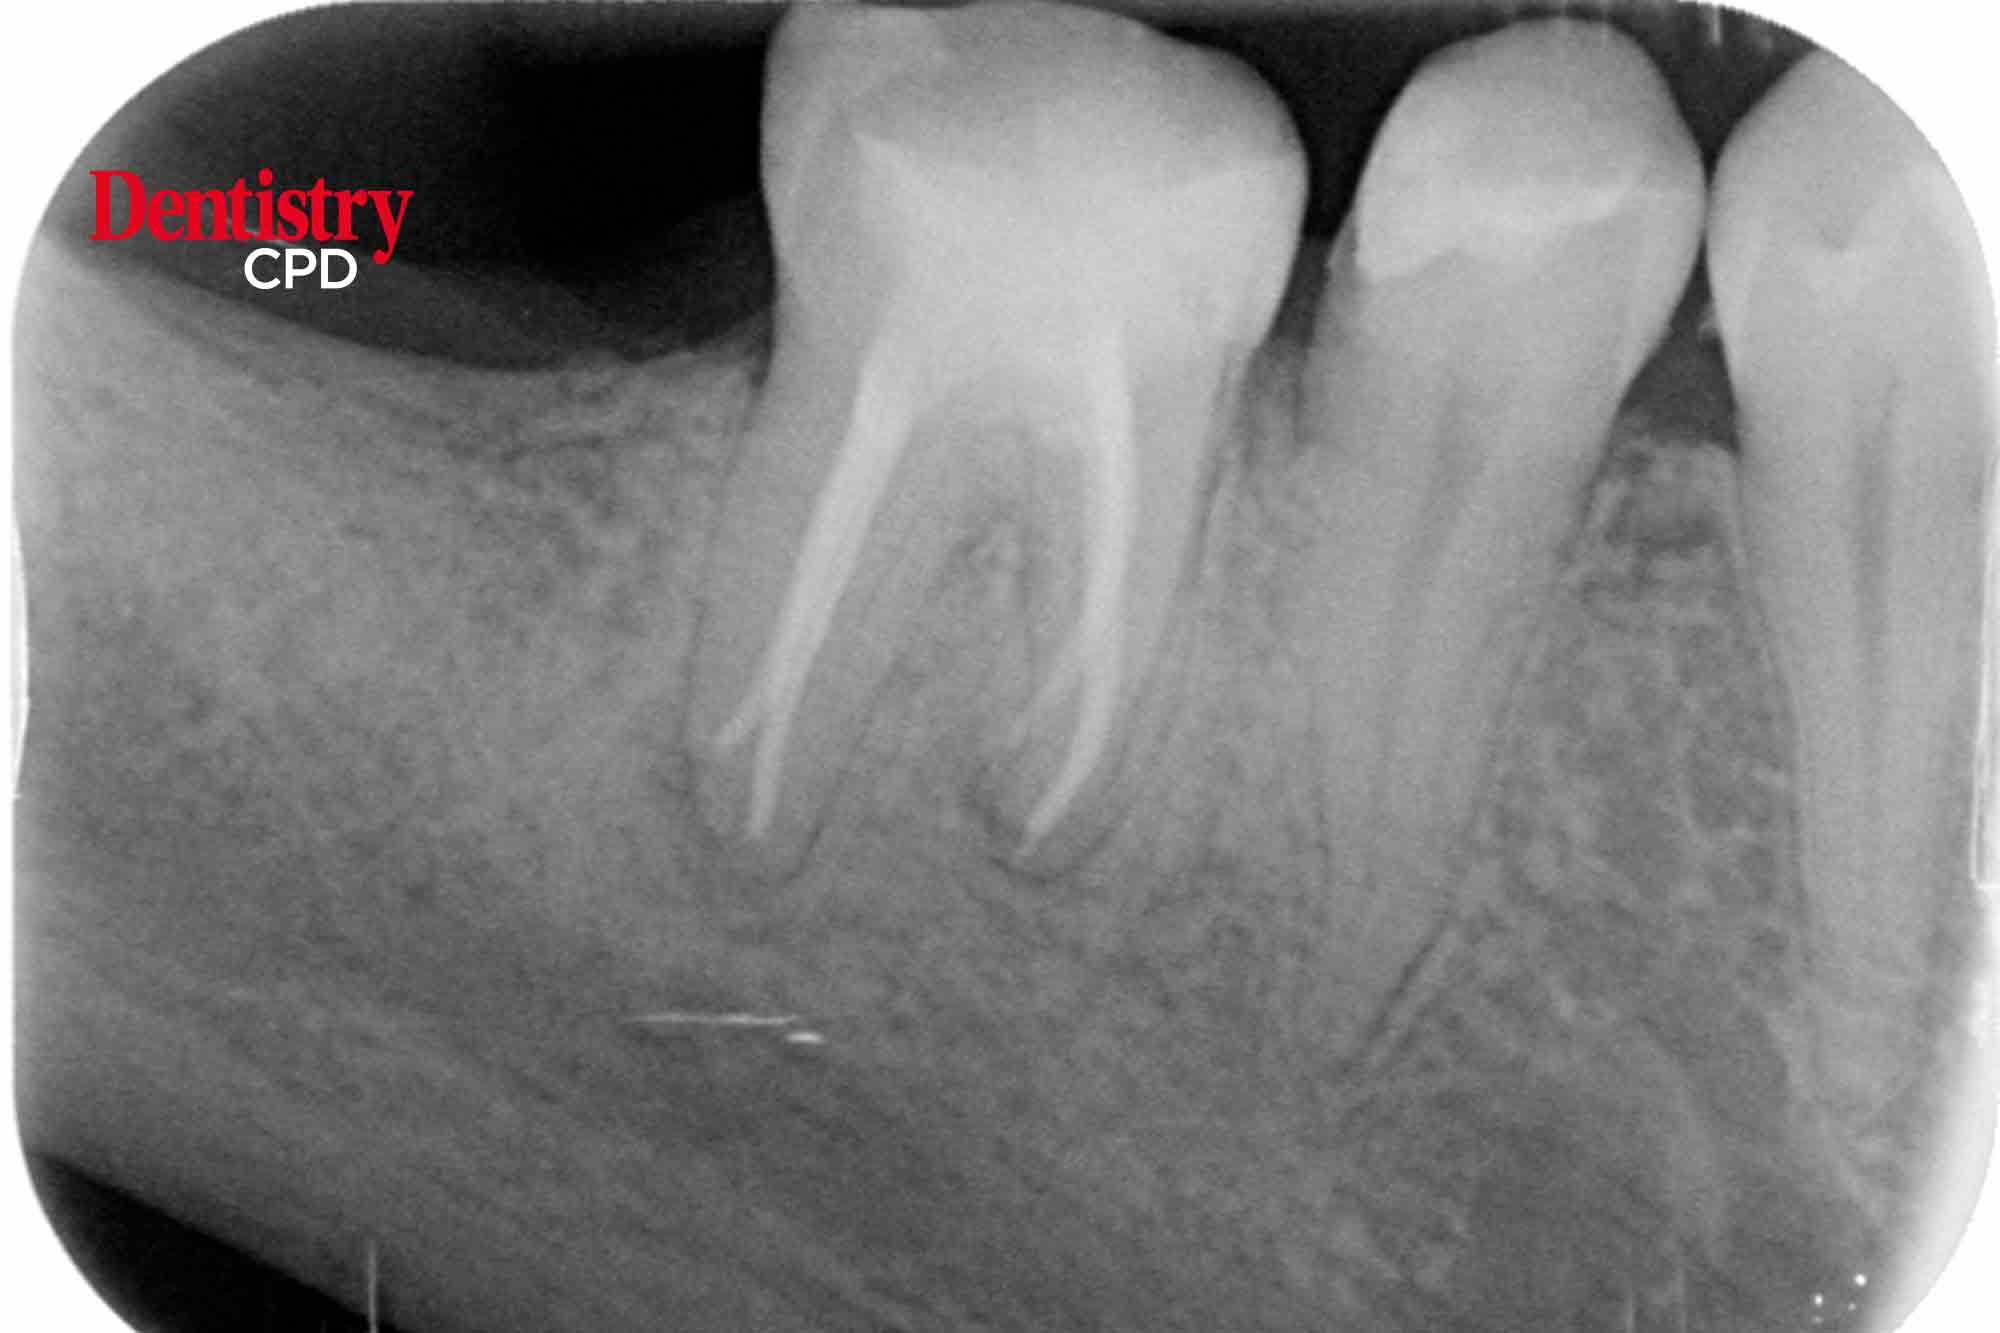

Dr Sagi Shavit presents an endodontic case which indicates how simplicity can lead to high-quality treatment delivery and a successful end result